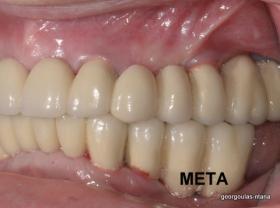

Η ασθενής αυτή είχε παλιές ακίνητες αποκαταστάσεις (γέφυρες) στην άνω γνάθο  κ μια κινητή προσθετική αποκατάσταση (μερική οδοντοστοιχία-"μασελάκι") στην κάτω γνάθο. Ήταν δυσαρεστημένη τόσο με την εμφάνιση όσο και με τη λειτουργία των δοντιών της καθώς παραπονιόταν ότι  είχαν εντονη κινητικότητα ενώ και οι προσθετικές τους εργασιές δεν ήταν σταθερές. Η πρόγνωση των δοντιών κρίθηκε φτωχή με αποτέλεσμα να μην είναι δυνατή η συμμετοχή τους σε μια νεα προσθετική αποκατάσταση με μακροχρόνια διάρκεια. Η ασθενής επιθυμούσε οι νέες αποκαταστάσεις να είναι σταθερές και ακίνητες.  Για το λόγο αυτό αποφασίστηκε η ολική αποκατάσταση της άνω κ κάτω γνάθου με ακίνητες επιεμφυτευματικές εργασίες. Στην αριστερή πλευρά της άνω γνάθου, λόγω μη επαρκούς οστού για την τοποθέτηση εμφυτευμάτων προηγήθηκε επέμβαση ανοιχτής  ανύψωσης ιγμορείου άντρου με τη χρήση πιεζοχειρουργικού μηχανήματος ώστε να δημιουργηθεί το κατάλληλο οστικό υπόστρωμα. Ακολούθησε σε επόμενο χειρουργείο η εξαγωγή των υπάρχοντων δοντιών κ η άμεση τοποθέτηση εμφυτεύματων (άμεση εμφύτευση) κ δύο μέρες μετά η τοποθέτηση προσωρινής εργασίας επί των εμφυτευμάτων (άμεση φόρτιση) με αποτέλεσμα η ασθενής να μη μείνει καθόλου χωρίς δόντια κ να είναι καλυμένη αισθητικά όσο καιρό διήρκησε η εργασία